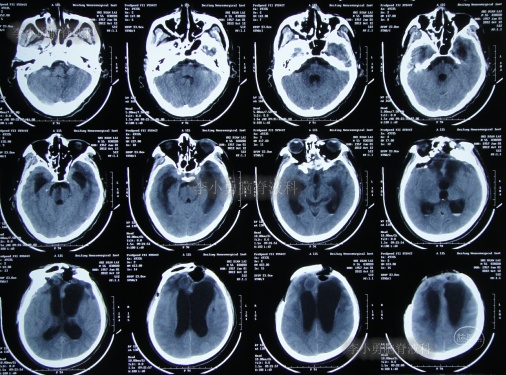

第3家医院出院后26天即2012年9月26日(开颅术后92天),因患者失语、嗜睡、吞咽障碍,第2次住入第3家医院,入院后2天即2012年9月28日,给予伤口及脑内脓肿清创缝合术+脑脊液漏修补术+右大腿取脂肪术,但术后2周即2012年10月12日,复查头颅CT提示脑积水(图-1)。

图-1:2012年10月12日头颅CT

2012年10月16日(第3家医院第2次住院20天),进行了脑室腹腔分流术(图-2)。

图-2:2012年10月16日头颅CT